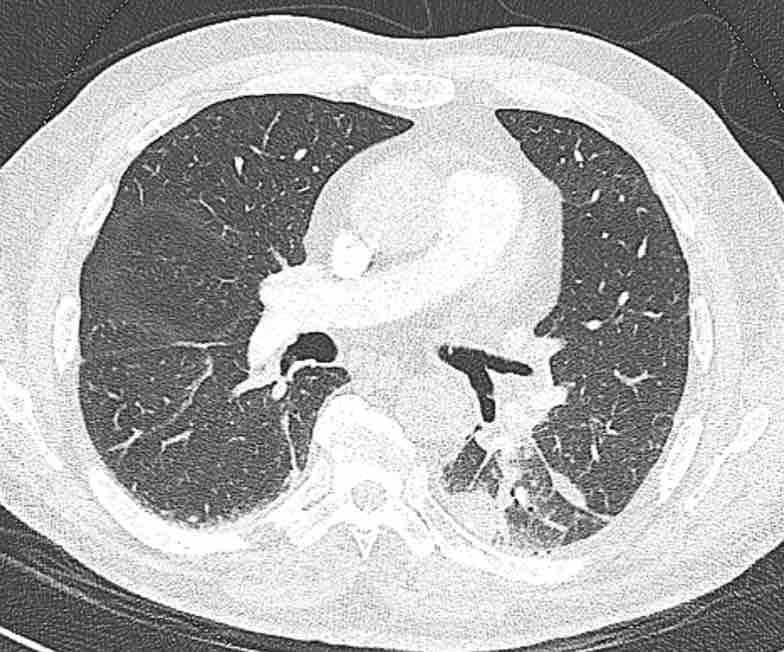

Hình ảnh

Cuộn qua các hình ảnh.

Theo dõi các phế quản của thùy dưới phổi trái cho thấy nhánh phân thùy đầu tiên của thùy dưới phổi trái còn thông; đó là phế quản phân thùy đỉnh.

Các ghim phẫu thuật nằm tại vị trí của các phân thùy đáy sau và đáy bên (LB9/10), vốn thường được cắt bỏ cùng nhau.

Do đó, phân thùy phổi có hình ảnh kính mờ và đông đặc phải là phân thùy đáy trước của thùy dưới phổi trái (LB8).

Động mạch phổi đến phân thùy này cũng không ngấm thuốc cản quang, và bản đồ tưới máu iốt nhấn mạnh thêm tình trạng nhồi máu.

Bệnh nhân đã được phẫu thuật lại và tiến hành cắt bỏ phân thùy bị nhồi máu, với xác nhận qua giải phẫu bệnh.

Tiếp tục với bản đồ tưới máu…

Trên bản đồ tưới máu iốt, có sự tưới máu ở thùy trên phổi trái và phân thùy đỉnh của thùy dưới phổi trái, nhưng không có sự tưới máu ở phân thùy đáy trước của thùy dưới phổi trái.